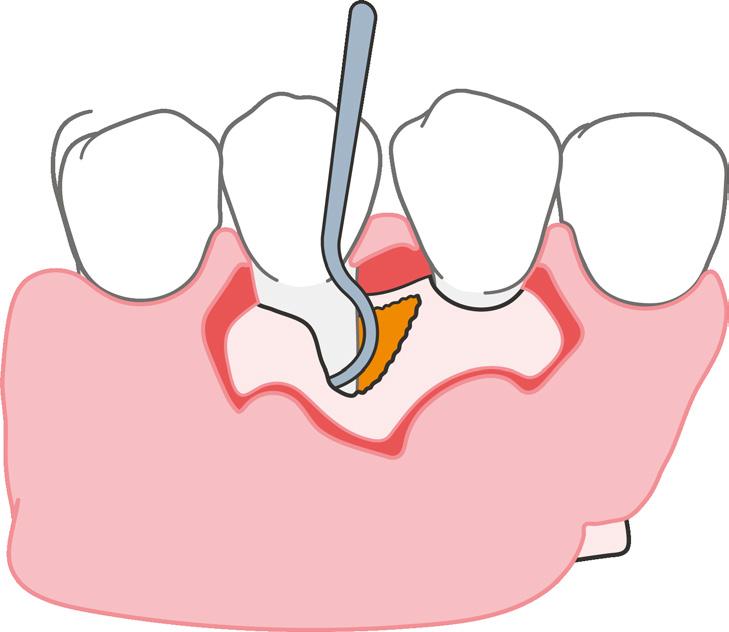

Los dientes anteriores (n.º 13 23) se feru lizaron con una férula periodontal Rib bond, y la oclusión se ajustó a un contac to ligero. Se elevó un colgajo de espesor total, y el defecto se descontaminó con una combinación de láser de CO2 de 9,3 micras y EDTA al 24 %. Después de la descontaminación confirmamos un de fecto de una pared con una bolsa perio dontal intraósea de 7 mm. Injertamos el defecto con Geistlich Bio‑Oss® Collagen, que tiene una excelente capacidad para actuar como andamiaje y resulta muy útil en esta indicación.1 Después cubrimos el injerto óseo con L PRF™ para una mejor respuesta angiogénica de los tejidos.

La microcirugía periapical regenerativa incluye los siguientes pasos (figura 1):

1. Aumento mejorado para una resección mínima de la raíz;

2. Preparación ultrasónica del ápice de la raíz;

3. Obturación retrógrada con un mate rial biocerámico para la reparación de la raíz; y

4. Regeneración tisular guiada en el lu gar del defecto óseo.